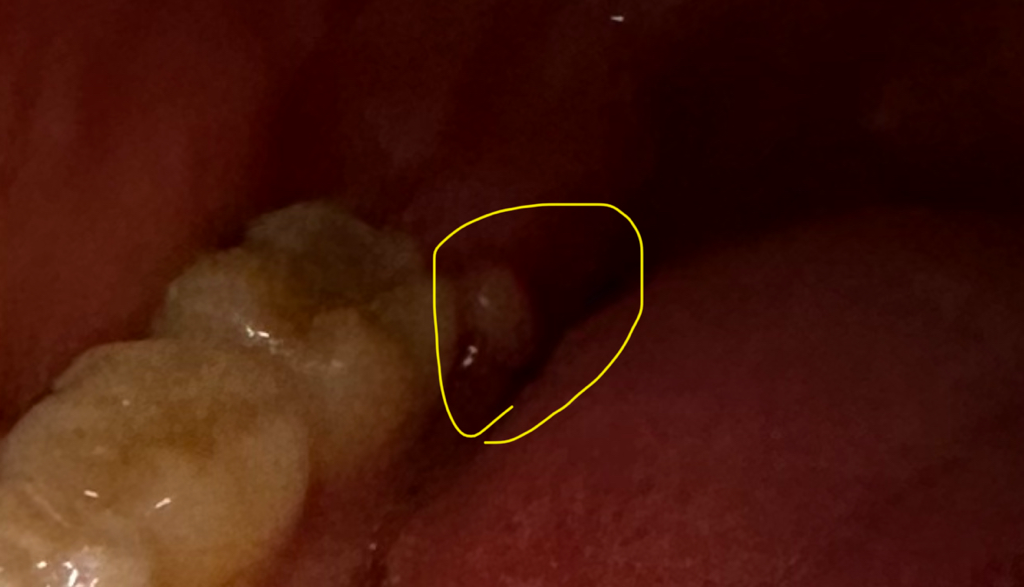

사랑니 발치 2주 흰색 고름 / 혹 / 농양 / 여드름 같은 거 단순 염증인가요 자연적 치유 되나요?

흰색 고름 / 혹 / 농양 / 여드름 같은 게 생겼어요

(흰색 진주 알 같은? 동그란 안터진 여드름 같은?

사이즈는 총알 보단 조금 작은 정도 )

• 1번 째 사진

사랑니 뽑은 부위 가장자리 잇몸에 덜 아문 것으로 보입니다. 희게 보이는 것은 딱지 앉은 것으로 보이며 시간이 지나면 점점 없어집니다.

사진상을 보면 크게 문제가 잇는건 아니고 잇몸이 약간 부어 잇는거 같습니다. 시간이 지나면 괜찮아 지실꺼에요.